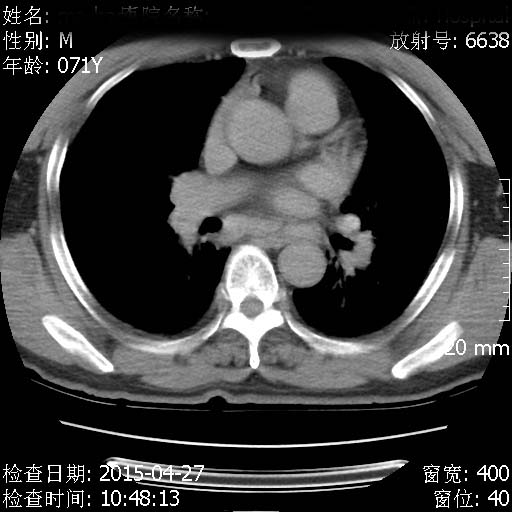

CT50343:胸部:男性 70岁 左上肺球形阴影。 ...

CT50343:胸部:男性 70岁 左上肺球形阴影。

本帖最后由 cefcmj 于 2015-4-28 12:34 编辑 胸痛、气短半月。测量CT值增高不明显。

左肺周围型肺癌伴双肺转移。

左肺周围型肺癌

左肺周围型肺癌可能性大。

左侧肺癌伴双肺转移。

双肺团块状高密度影,可见胸膜凹陷征,肺门淋巴结肿大。考虑 多发周围性肺癌伴肺门淋巴结增大。 结节病不除外。

左侧中央型肺癌